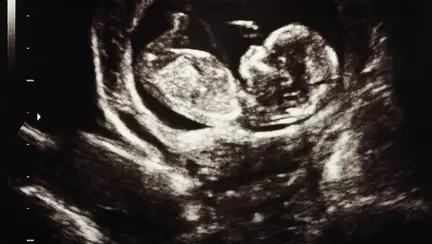

Deşi la început sarcina evoluează normal şi nu prezintă probleme, la un moment dat semnele specifice sarcinii dispar: uterul nu se mai măreşte, greaţa şi vărsăturile încetează, uneori apare po mică sângerare vaginală. De cele mai multe ori însă, sarcina oprită în evoluţie nu dă mult timp simptome, ea fiind depistată în timpul examenului ecografic,